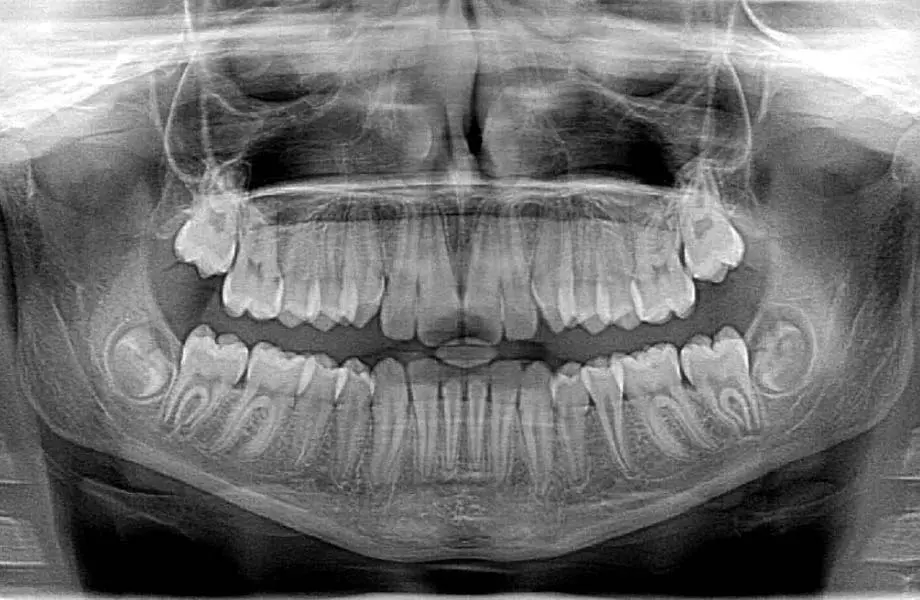

1 나는 안세보고도 내 치아 개수를 바로 말할 수 있다

Vs

2 손가락 발가락도 아니고 개수를 기억하고 살진 않는다

참고) 보통 성인은 32개의 치아를 갖고있지만 사람마다 다를 수 있다고 함 !